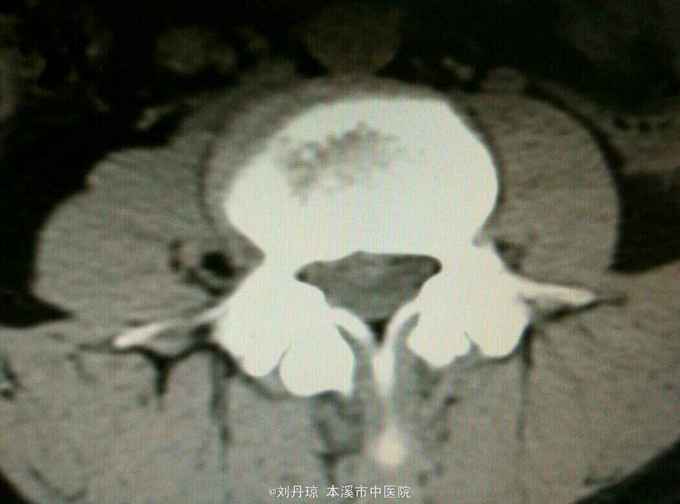

腰部疼痛伴右下肢放射痛麻木感1年,加重1月。患者1年前劳累后感到腰部疼痛伴右下肢放射痛麻木感,近1月病情加重来诊。

查体:L3—S1棘突右旁压痛阳性。直腿抬高实验左70度,右40度。 直腿抬高加强实验左侧阴性,右侧阳性。腰椎功能障碍。 辅查:CT: L3—S1椎间盘突出。

诊断:腰椎间盘突出症 治疗:针灸、雷火灸、中药熏药治疗、小针刀治疗、骶管注射治疗、营养神经药物治疗、脱水药物治疗,当归地黄饮加味。